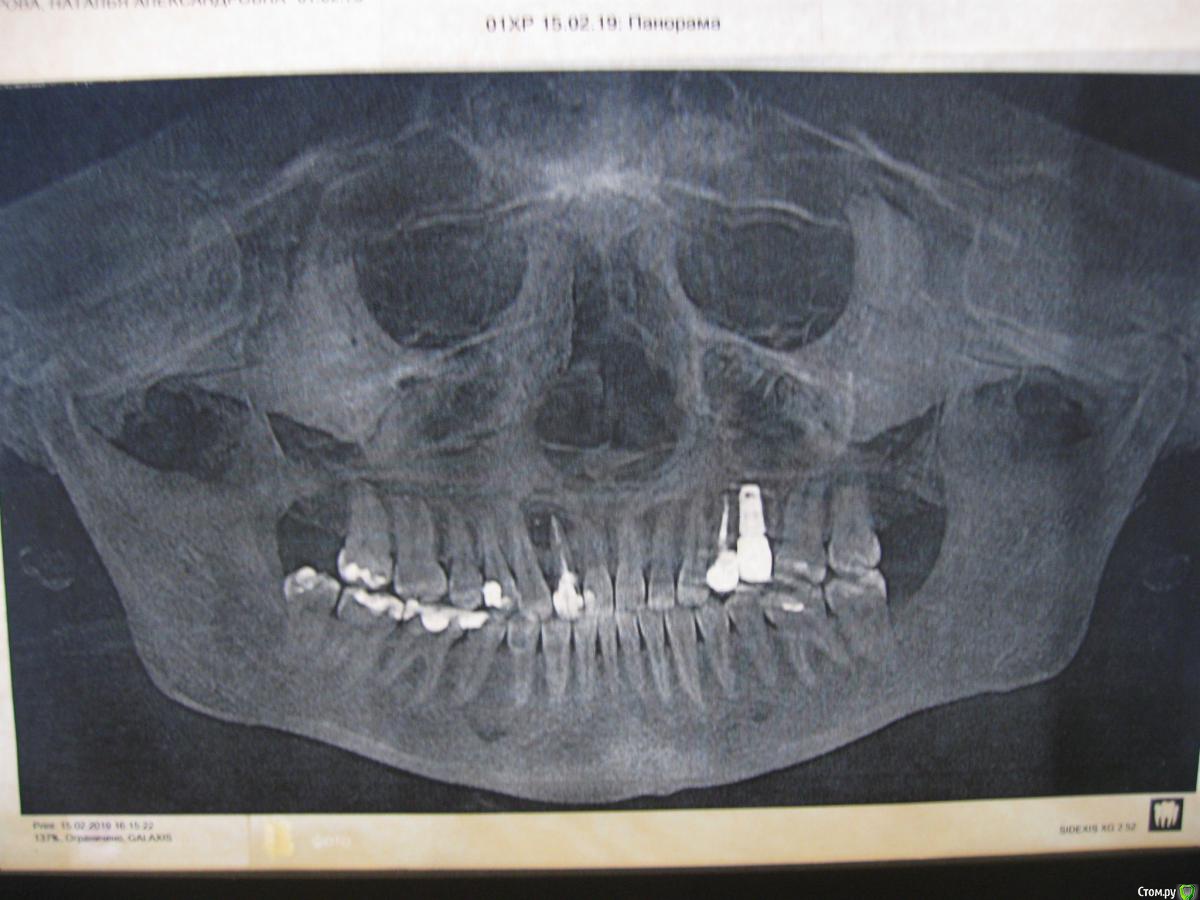

Здравствуйте. Интересует ваше мнение по поводу 12 зуба с кистой. Киста обнаружена примерно год назад случайно. Первоначальный размер примерно 8 мм*10 мм, снаружи на десне был небольшой дефект примерно 3 мм (снимка первого у меня нет).

Проводилось эндодонтическое лечение в течение почти 5 месяцев (промывания, закладывание лекарства, временная пломба). Во середине лечения болела ОРВИ, в результате был перерыв и ухудшение состояния зуба.

Постоянно запломбирован в сентябре 2018 г. По прошествии 4-х месяцев  киста не уменьшилась,  В январе снова ОРВИ - наружный дефект значительно увеличился, доктора говорят, что свищ, но я не наблюдаю из него оттока. По снимку на сегодняшний день киста кажется подросла.

Терапевт, который лечил, предлагает сделать резекцию. Была на консультации у двух хирургов - один считает резекцию бессмысленной и предлагает удаление, со временем имплант, другой считает, что хирургия не нужна, можно вылечить.

Здравствуйте , ОПТГ не дает полной картины , состояние зуба (той части что вам видна ) под вопросом и возможно не состоятельна - тогда удалять . если же коронковая часть зуба способна нести нагрузку , и по КТ объемы кисты будут соответствовать Вашему снимку , то проблем для выполнения резекции не вижу.

P\S: боюсь , что та часть что над десной уже в плохом состоянии - такие вещи иногда пока не раскроешь и не вычистишь , не узнаешь удалять или нет.